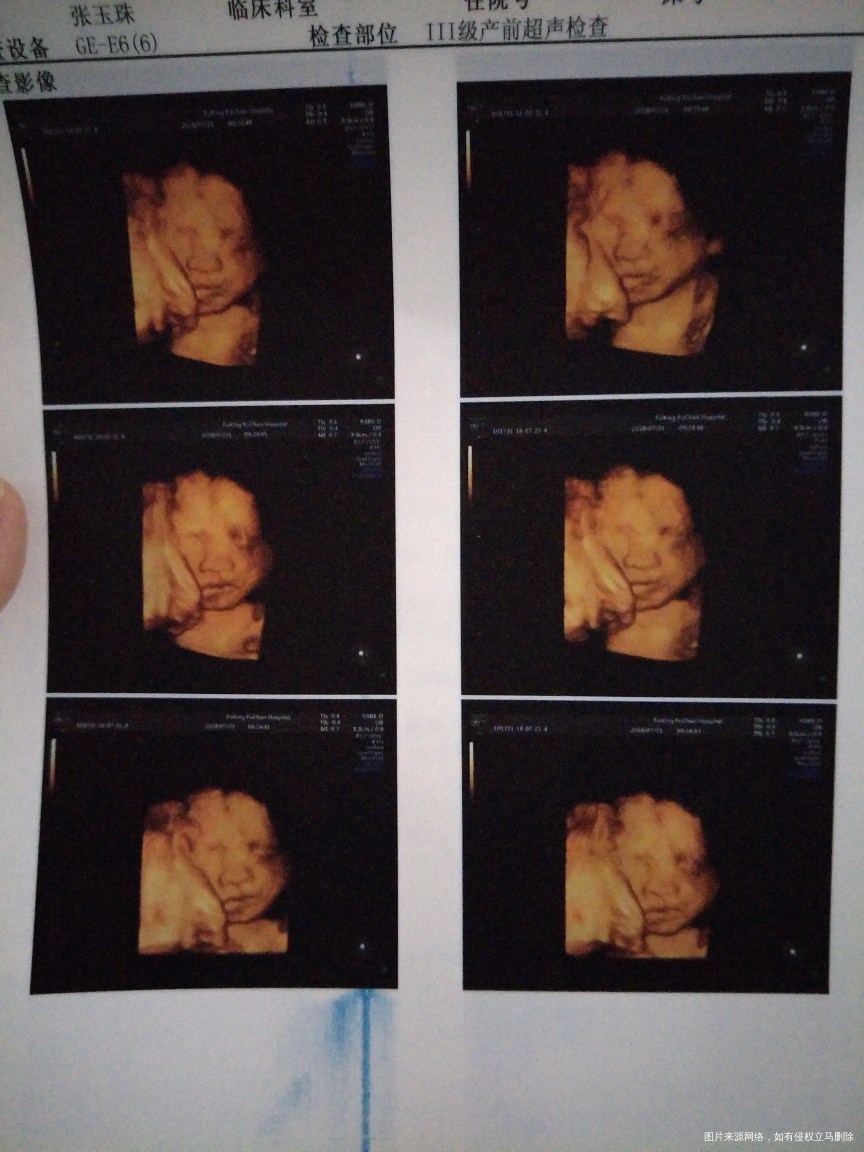

怀孕26+6,做的四维彩超,看不见宝宝的手指头和脚指头,正常吗?好担心啊,麻烦医生帮忙看看,

你好,宝妈。宝宝总体发育均正常,至于手指脚趾不清楚,多半宝宝体位有关。之后可以再次复查,定期产检,祝你好孕。如果我的建议对您有帮助,请记得选择点击采纳哦。

补充说明:宝妈可以了解彩超最下面几行的说明,手脚,耳等等不是彩超检查的项目,因为毕竟宝宝在子宫内,除非MRI或是更高超的检查才能看见“细枝末节”。目前已经接近孕晚期,注意宝宝胎动,定期产检,祝你好孕。如果我的建议对您有帮助,请记得选择点击采纳哦。